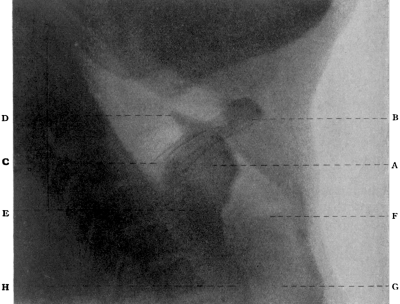

| 334. | Radiograph to show the Value of the Röntgen Rays | 639 |

| 335. | Radiograph showing Canula in the Frontal Sinus | 639 |

| 343. | Radiograph of the Sphenoidal Sinus | 653 |

| 344. | Radiograph of the Sphenoidal Sinus | 653 |

| 347. | Radiograph showing a Probe in the Sphenoidal Sinus | 657 |